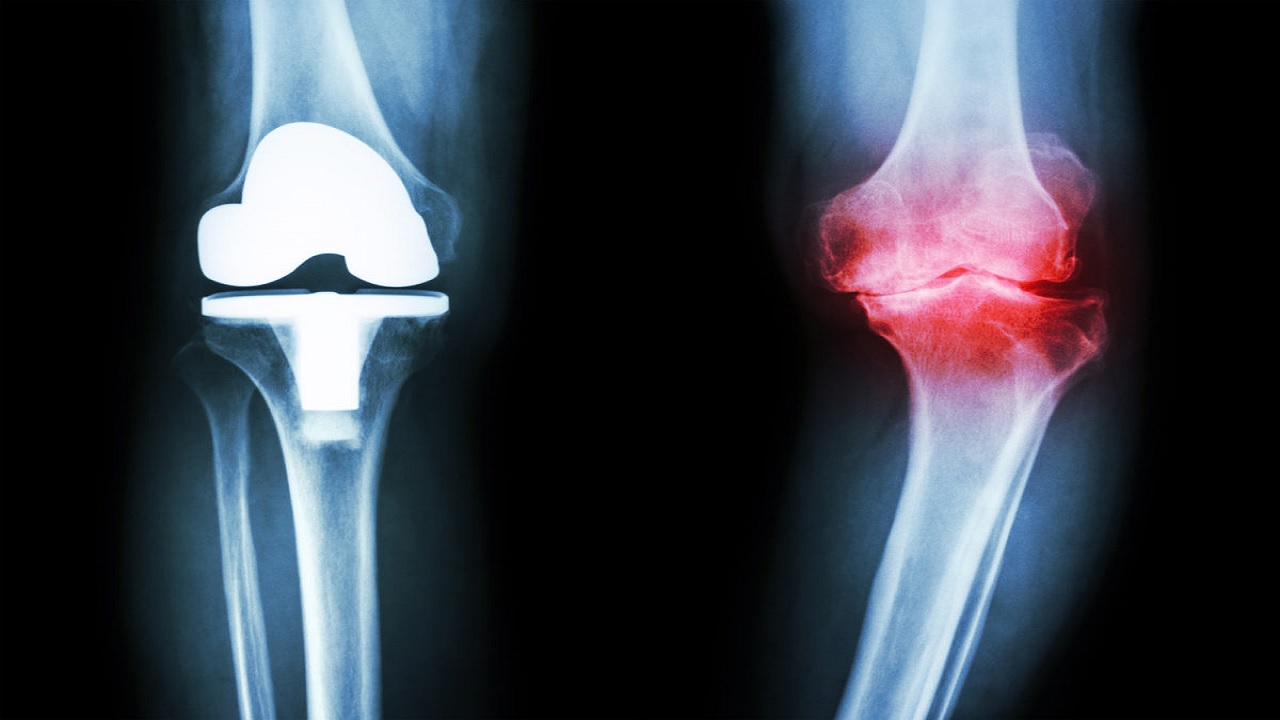

به گزارش ، آرتروز زانو امروزه یکی از بیماریهای بسیار رایج در میان افراد سالمند است. آرتروز مفصل زانو شایعترین بیماری سوختگی با آب جوش تخریبی از میان مفاصل بدن محسوب میشود و احتمال ابتلای زنان به آن بیشتر از مردان است. عوامل زیادی مانند: کهولت سن، مسائل ژنتیکی و وراثتی، نوع شغل، چاقی، عوامل هورمونی و نژادی در بروز این بیماری دخیل هستند. در این بیماری غضروف مفصلی به تدریج شروع به تخریب شدن میکند و در نتیجه آن بیمار از درد ژل کیتوهیل شدید در زانوهای خود گلایه دارد. حال دانشمندان موفق شده اند به روشی ساده برای تسکین درد این بیماری دست یابند.

در این تحقیقات دانشمندان به مدت ۱۲ هفته اقدام به استفاده از عصاره زردچوبه بیماران مبتلا به آرتروز زانو کردند. شواهد نشان داد به میزان قابل توجهی از درد این بیماران کاسته شده، اما تصاویر ام آر آی نشان داد مصرف این عصاره تاثیری در ساختار زانو یا بهبودی بیماری نداشته است.